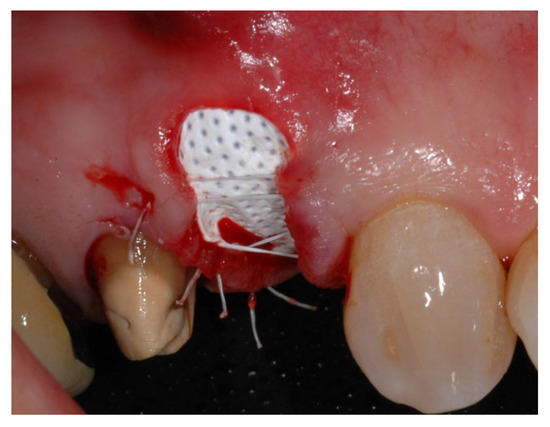

2.2. Clinical Procedures